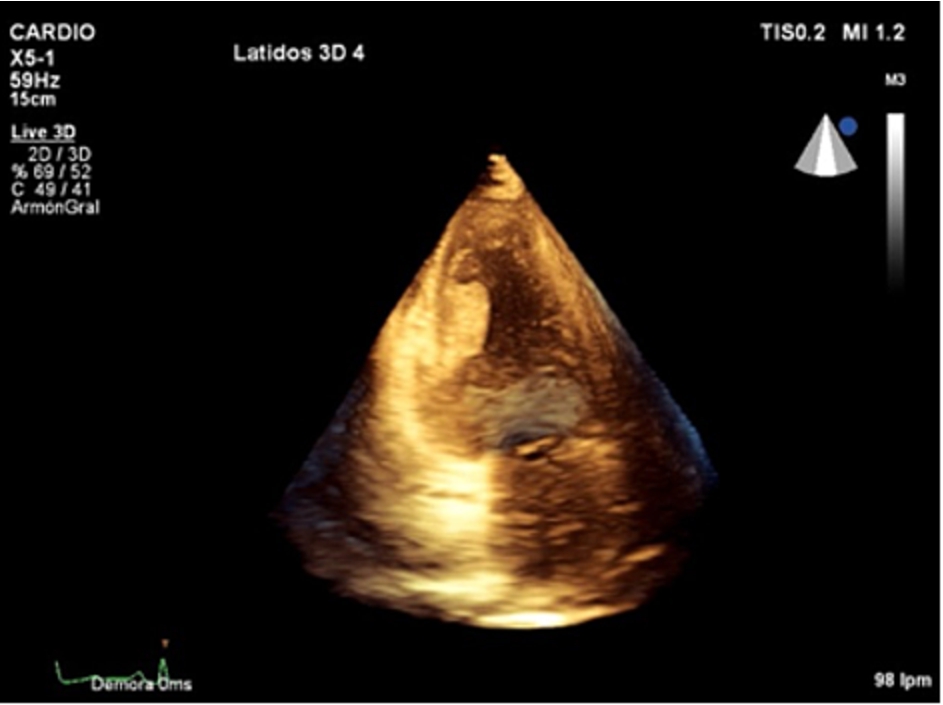

Figure 3.

3D-transthoracic echocardiogram. Apical two-chamber view. Mass attached to the left ventricular inferior wall.

Conventional transthoracic echocardiography was repeated a week later, without changes. 2D-echocardiographic study was completed with intravenous echocardiographic contrast to demonstrate perfusion of the mass, excluding the diagnosis of thrombus (Movie II in the Data supplement) and with 3D echocardiography for better visualization and establishing spatial relationships of the mass (Movie III and Movie IV in the data supplement).

The patient had poor outcome and died, autopsy was not performed and therefore histologic study of the mass was not available. Although the PET study showed perfusion of the mass and contrast echocardiographic study demostrated perfusion. Based on the clinical scenario and the PET, 3D-transthoracic echocardiogram and contrast findings, the mass was suspected to be a cardiac metastasis. These images show sole intracardiac mass (probably metastasis) with no other cardiac involvement in a patient with metastatic lung cancer disease. This is an unusual case because of the atypic pattern of metastases in the heart [1], that more often is characterized by pericardial effusion and local extension [2] or involvement and atrial masses with invasion to the heart by the pulmonary veins [3]. Haematogenic dissemination is the most probable mechanism for this case. Three-dimensional echocardiography is useful in diagnosis and monitoring of myocardial masses [4, 5].